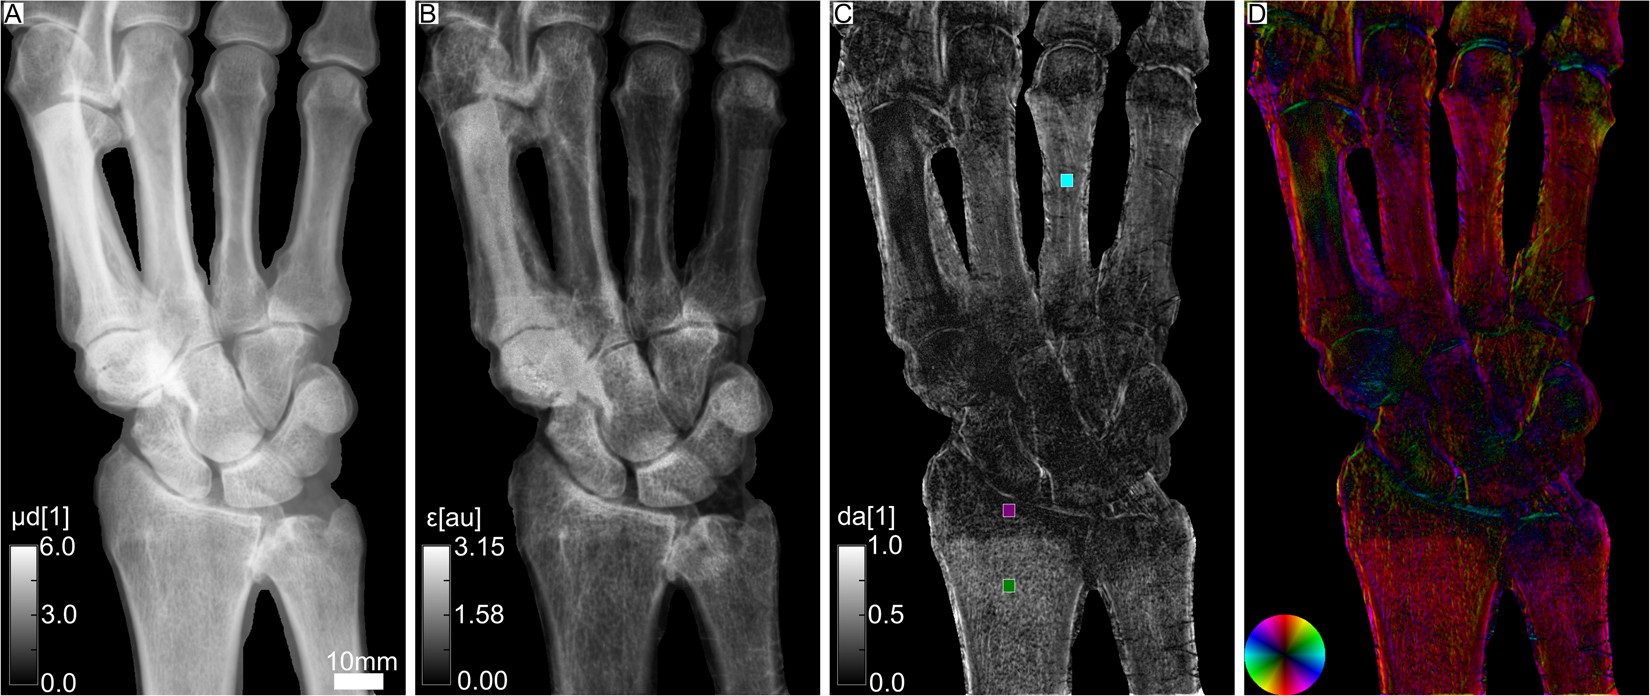

Figure 2

From: Trabecular bone anisotropy imaging with a compact laser-undulator synchrotron x-ray source

Attenuation and XVR images of a human hand, showing the radius, ulna, carpals and metacarpals. In (A) the integrated attenuation coefficient is depicted. (B) Depicts the mean scattering strength. (C) Illustrates the degree of anisotropy, i.e. the difference of maximum and minimum scattering divided by its sum. The mean values in the colored ROI’s are dacyan = 0.27, dapurple = 0.08 and dagreen = 0.41. In (D) the orientation of scattering structures is color-coded according to the color wheel shown in the bottom left. Brightness once again corresponds to the degree of anisotropy.